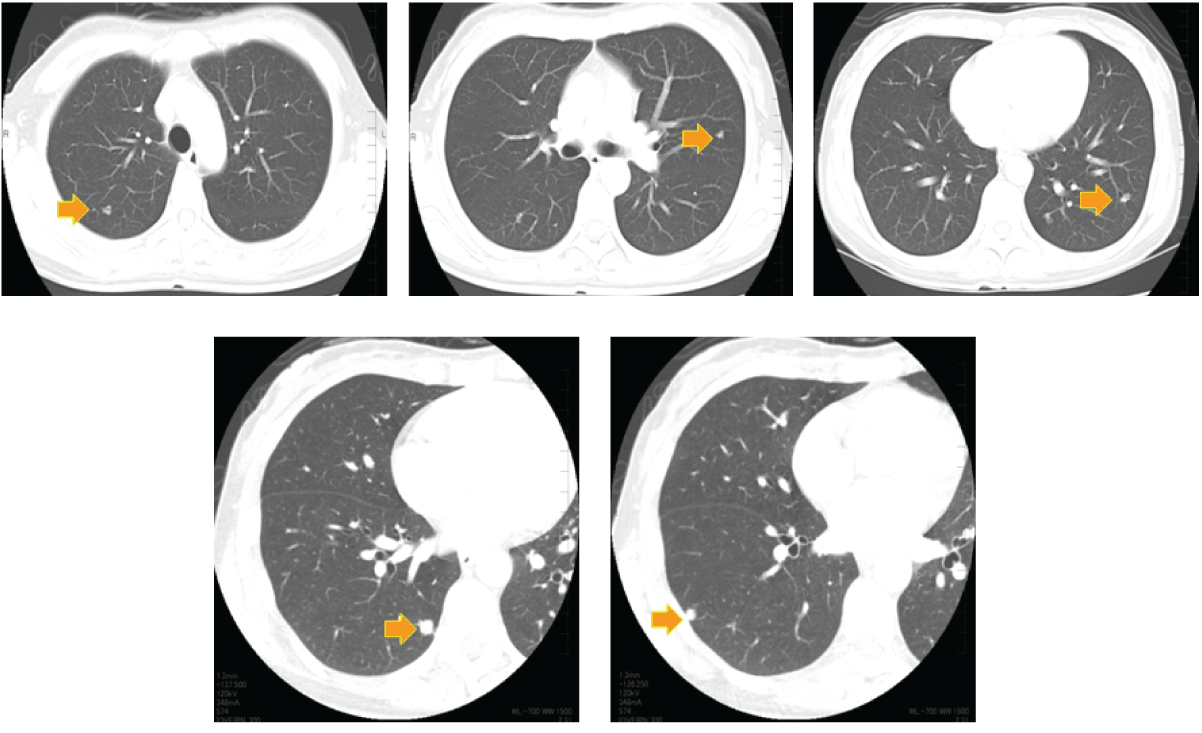

Computed tomography (CT) scan showed bilateral, nodular, lung shadows in an asymptomatic 38-year-old female. (Figure 1) Five nodules up to 10 mm each were identified in the right and left lungs. She was followed-up for four months, during which the size and density of these shadows remained unaltered. The patient requested a definitive diagnosis and underwent a video-assisted thoracoscopic lung biopsy of two lesions in the right lower lobe (S6c, S9a). A histopathological examination showed vacuolated tumor cells, immunohistochemical staining of which was positive for the endothelial marker CD34. Electron microscopy identified Weibel-Palade bodies. These findings supported a diagnosis of pulmonary epithelioid hemangioendothelioma (PEH). (Figure 2) All other organs were free of abnormalities and the patient was remained under observation for two years without treatment or disease progression.

Figure 1: Computed tomography scan of chest. Bilateral, multiple, nodular, lung shadows range in size up to 10 mm.